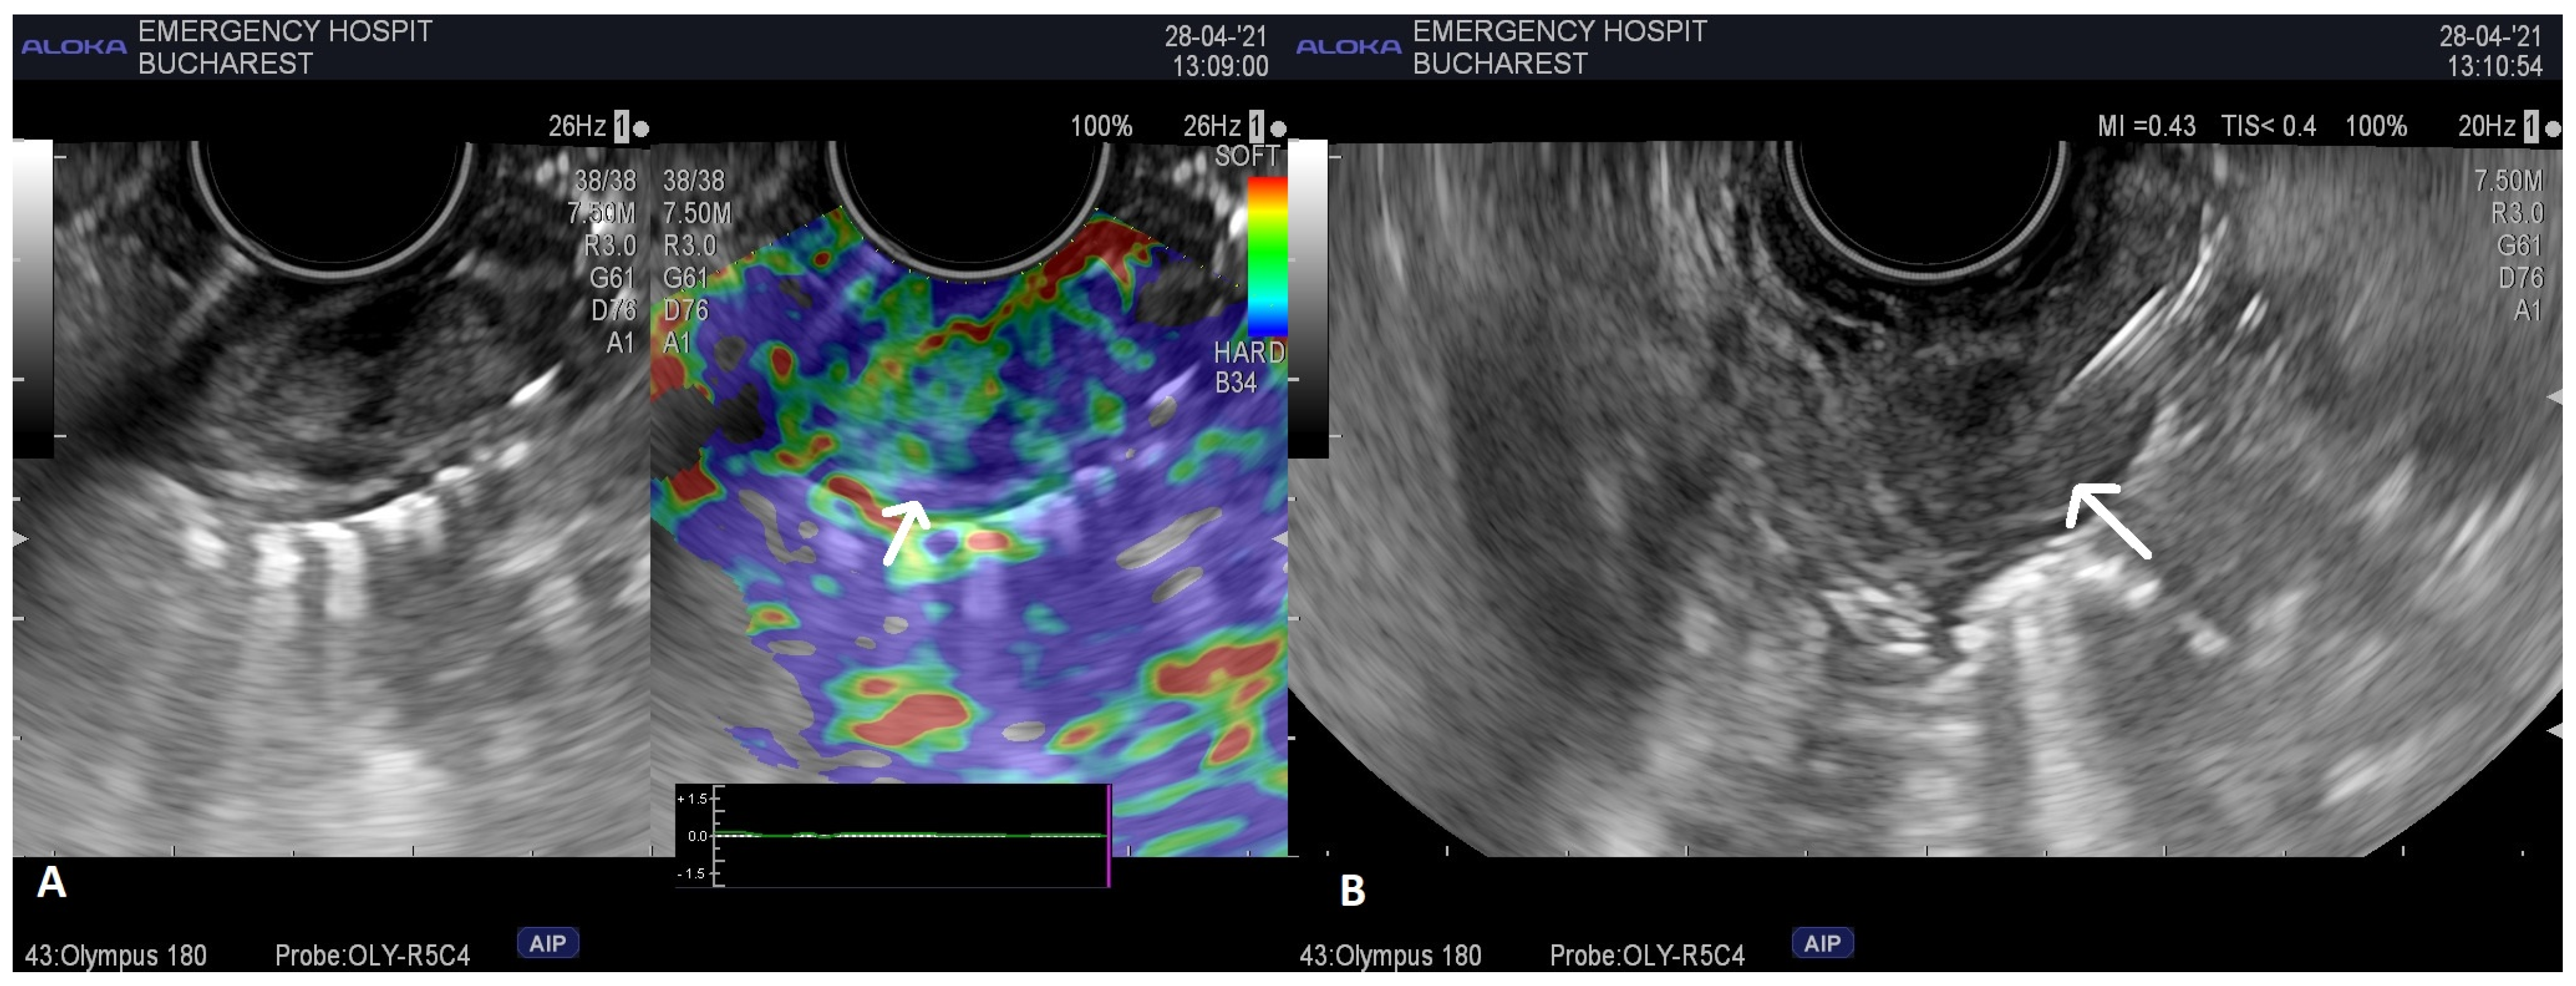

2. Case Report 1

3. Case Report 2

4. Case Report 3